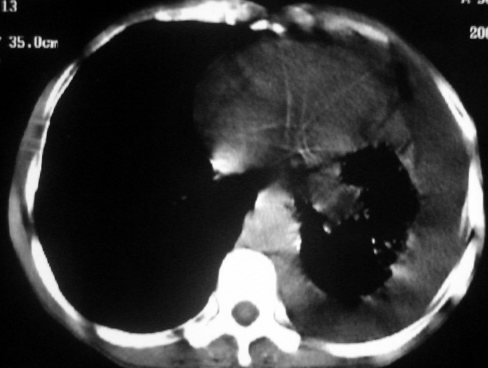

男,54岁,咳嗽,气喘半年,胸痛一月.

血性胸水

左侧胸腔积液 斜裂积液 心包积液 左肺不张 考虑左肺ca并胸膜心包转移。

支持左肺下叶中心型肺癌(累及舌叶)伴阻塞性肺炎、膨胀不全、胸腔积液、心包少量积液。

考虑左肺下叶中央型肺癌伴阻塞性肺炎及肺不张,纵隔受累可能,胸膜转移。